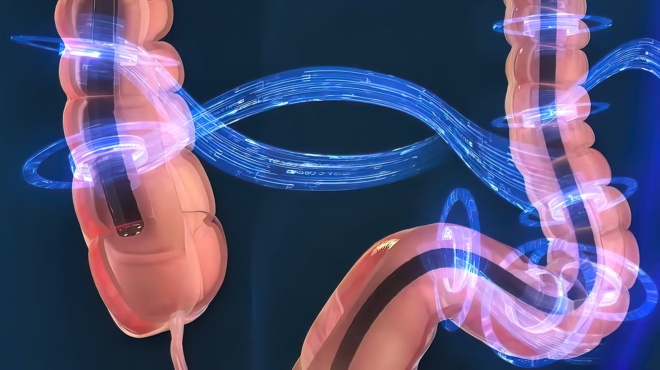

Η πρώτη στον κόσμο τυχαιοποιημένη μελέτη της χρήσης κολονοσκόπησης για την πρόληψη του ορθοκολικού καρκίνου (του παχέος εντέρου) δείχνει ότι η εν λόγω εξέταση δεν αποτρέπει τη θανατηφόρο νόσο τόσο αποτελεσματικά όσο είχε προηγουμένως θεωρηθεί.

Η μελέτη NordICC (Nordic-European Initiative on Colorectal Cancer), με επικεφαλής τον καθηγητή Μίκαελ Μπρετχάουερ του νορβηγικού πανεπιστημίου και του Πανεπιστημιακού Νοσοκομείου του Όσλο, η οποία παρουσιάστηκε στο ευρωπαϊκό γαστρεντερολογικό συνέδριο της United European Gastroenterology «2022 UEG Week» στη Βιέννη και δημοσιεύθηκε στο διεθνούς κύρους αμερικανικό ιατρικό περιοδικό «New England Journal of Medicine», ανέλυσε στοιχεία για σχεδόν 85.000 υγιείς ανθρώπους 55 έως 64 ετών σε τέσσερις ευρωπαϊκές χώρες (Νορβηγία, Σουηδία, Πολωνία και Ολλανδία).

Οι συμμετέχοντες χωρίστηκαν τυχαία σε δύο ομάδες: Η μία έκανε έλεγχο εντέρου με κολονοσκόπηση, ενώ η άλλη καμία εξέταση. Όλοι οι άνθρωποι παρακολουθήθηκαν επί δέκα χρόνια -κατά μέσο όρο- για να διαπιστωθεί σε ποιον βαθμό η κολονοσκόπηση, όντως, μειώνει την πιθανότητα διάγνωσης καρκίνου του εντέρου και θανάτου.